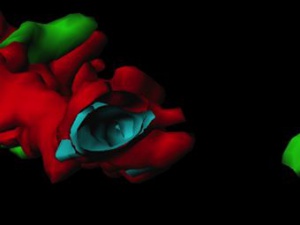

Konfokální mikroskopie umožňuje rychlé a velice kvalitní snímání ve vysokém rozlišení. Získaná data ve formě optických řezů je nutné rekonstruovat a následně analyzovat. Kolokalizační studie (3D colocalization) je spolehlivá metoda, která odhalí strukturní vztahy mezi zobrazovanými objekty.

Konfokální mikroskopie umožňuje rychlé a velice kvalitní snímání ve vysokém rozlišení. Získaná data ve formě optických řezů je nutné rekonstruovat a následně analyzovat. Kolokalizační studie (3D colocalization) je spolehlivá metoda, která odhalí strukturní vztahy mezi zobrazovanými objekty.

V laboratoři Dr. Xaviera Forns (IDIBAPS&NIH) se věnují výzkumu kinetiky viru Hepatitis C pro lepší porozumění průběhu opakované infekce tímto virem po transplantaci jater. Hlavním bodem zájmu bylo porovnání exprese receptoru viru Hepatitis C s celkovou kinetikou infekce.

Tato studie společně s dalšími výsledky ukázala, že množství receptoru viru Hepatitis C v čase transplantace jater reguluje počáteční kinetiku viru. Opakovaná infekce virem Hepatitis C po transplantaci je přímo spojena s množstvím těsných spojů v membránách jaterních buněk.